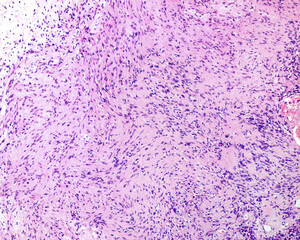

Neurilemmoma or schwannoma..

Neurilemmoma or schwannoma